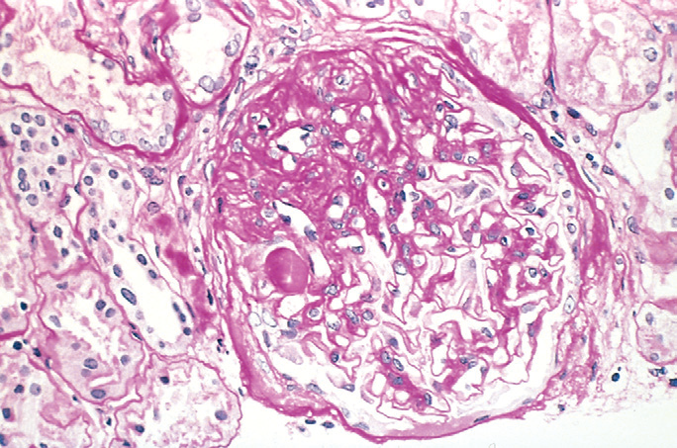

What is this and why?

FSGS because only part of the glomeruli is carred, and only some glomeruli are effected